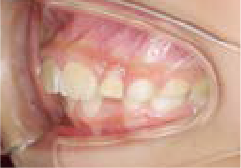

Before

After

上あごの成長が少なく、特に前歯のガタガタが目立っていました。口呼吸のクセや飲み込み方に良くないクセが確認されました。

治療を終えて

マイオブレイスとBB1装置で上あごの成長を助け、鼻呼吸や正しい飲み込み方を身につけることで、きれいな歯並びとしっかり噛めるお口に変わっていきました。

姿勢やお口の機能を正しく整えたので、後戻りしない綺麗な歯並びを維持できています。もちろん非抜歯です。

主訴・治療内容 当院と交流のある歯科医師の先生が、ご自身のお子さまの治療を任せてくださいました。

「難しい歯並びでも永久歯を抜かず、全身の健康と顔立ちも考えて治療してくれる」と信頼していただいて治療開始。

治療期間 3年

費用 462,000円(税込)

リスク・副作用

• 治療の初期段階では、痛みや不快感が生じやすくなりますが、一週間前後で慣れます。

• 歯の動き方には個人差があるため、予想された治療期間より延長する場合があります。